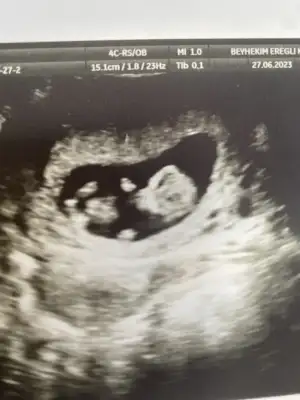

Merhaba 11 haftalık hamileyim bende bir aksilik olmazsa Aralık sonu ile 13 Ocak'a kadar doğum bekliyorum :) Biz cinsiyetini hala sormadık ve öğrenmedik bir süre daha öğrenmeyi düşünmüyorum, eskiden hep kız çocuk isterdim ama nedense oğlum olduğunu hissediyorum,